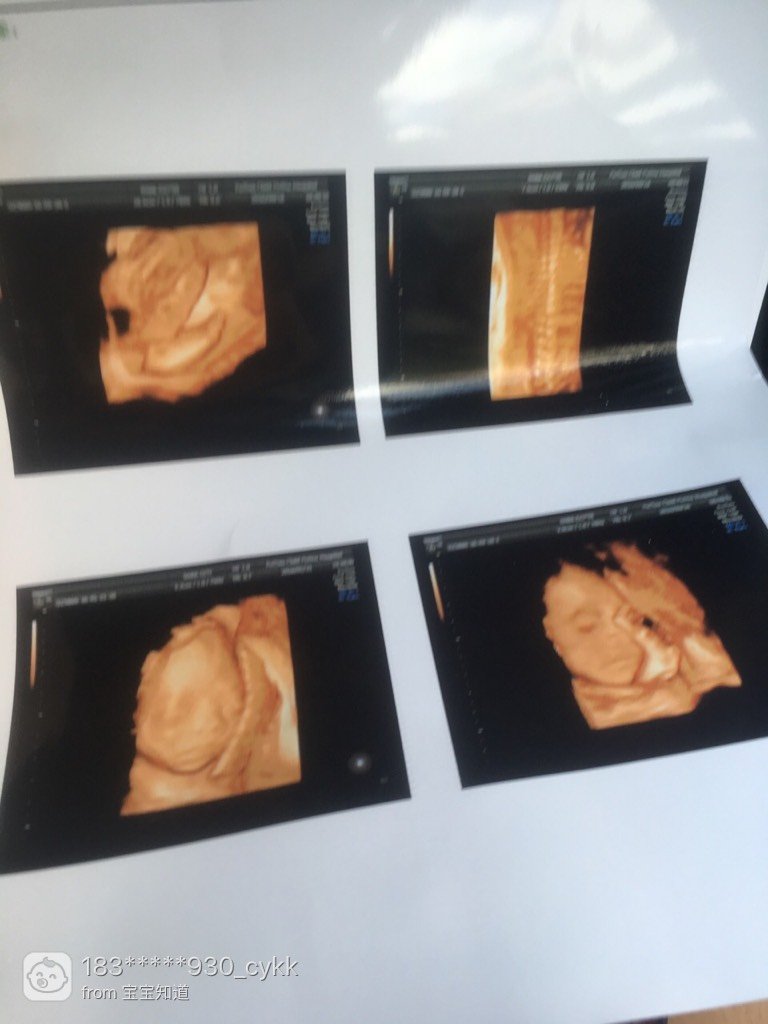

有那个宝妈会看男女的,帮忙看看,谢谢了

女孩